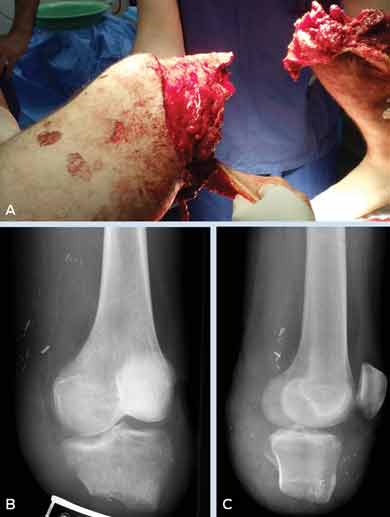

This is the first published case series of patients with injuries from watercraft propellers and jet skis. Five patients presented to the level-one trauma centre of Western Australia with such injuries over 10 days during the 2010–2011 Christmas holidays; all required surgery, and all but one sustained multiple, severe injuries. (MJA 2011; 195: 000-000)

Watercraft and propeller injuries are often characterised by severe initial injury and physiological insult, including severe haemorrhage. The cutting nature and high speed of propellers results in repeated wounding of the body at multiple levels, greatly multiplying the risk of irreparable damage to deep neurovascular structures. Also, serious complications can ensue after the initial damage control period, particularly uncontrollable wound infection, often with unusual bacteria which may not be detected by routine culture methods.2,3 This may necessitate amputation, even if a limb may initially appear to have been saved.